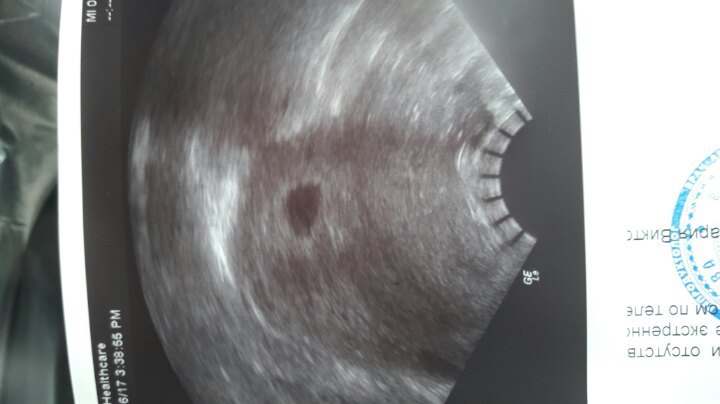

- УЗИ органов малого таза (отсутствие плодного яйца в полости матки, визуализация неоднородного объемного образования в области придатков на одной стороне и наличие свободной жидкости в полости малого таза

Если врач сочтет это необходимым, можно провести УЗИ, чтобы определить, присутствует ли развитие плодного мешка и плода соответствующим образом. Оно поможет подтвердить, что кровотечение было вызвано имплантацией эмбриона, а не сигнализирует о выкидыше.